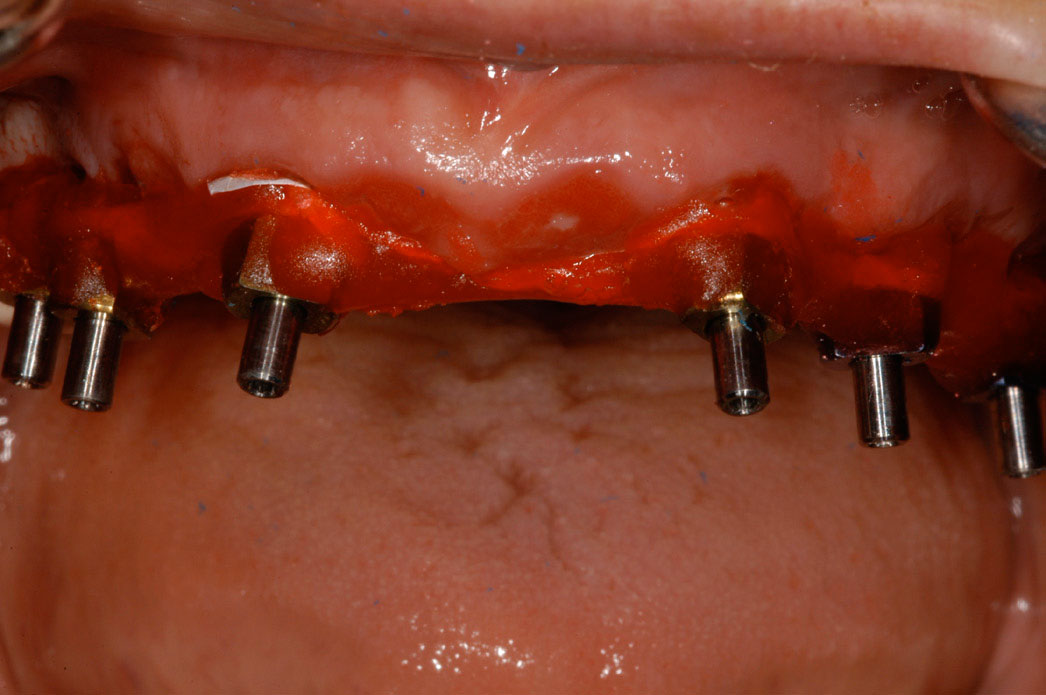

As stated earlier, dentures replace approximately 10% of chewing function. This causes digestive problems due to an inability to chew the food properly, also leading to malnutrition, due to eating only softer, more processed foods. Atrophy of the alveolar arches occurs due to lack of adequate pressure on the bone. This atrophy results in resorption of the tissues leading to mouth sores and tissue irritation. When the denture is allowed to irritate the mental foramen, the patient can experience pain and numbness of the lower lip. A positive solution for a denture patient is to have two to four implants inserted into the alveolar bone. The denture is then connected to the implants via snap-on attachments or a bar resulting in stabilization (Figure 21 through Figure 23). According to the 2002 McGill Consensus Statement on overdentures, mandibular two-implant overdentures are superior to conventional dentures in all clinical trials, even up to 9 years following insertion.36

Figure 22 – Maxillary bar that attaches the overdenture

Figure 22

Figure 23 – Fully edentulous patient restored with maxillary and mandibular implant supported implants

Figure 23